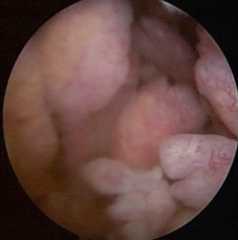

Arthroscopic images in RA: Exuberant synovial growth with villi-like proliferation

Image: “Arthroscopic image of synovial growth” by Department of Orthopaedics, Grant Government Medical College & Sir J.J. Group of Hospitals, Byculla, Mumbai, India. License:CC BY 4.0

Arthroscopic image of synovial proliferation of the knee in a patient with RA